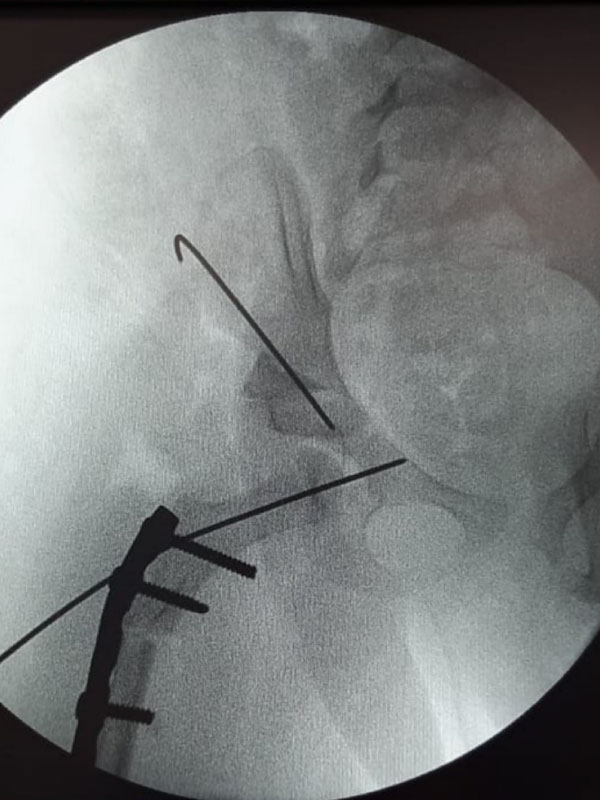

Caso No. 7 - Displasia de cadera derecha y síndrome down

Paciente femenino de 4 años de edad. Rx preoperatoria

Transoperatoria de Acetabuloplastia

Diagnóstico: Síndrome de Down con Displasia de cadera derecha con luxación.

Posoperación luego de la reducción abierta

Tratamiento quirúrgico realizado: Rx posoperatoria luego de la reducción abierta, acetabuloplastía y acortamiento femoral.